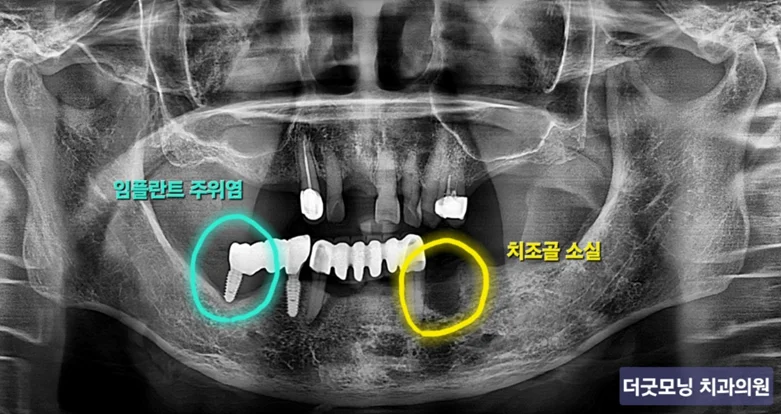

▶ 파노라마 엑스레이: 오른쪽 하악 임플란트 나사산 전체 노출, 왼쪽 치조골 소실 확인

파노라마 방사선 사진 — 오른쪽 임플란트 나사산 노출, 왼쪽 치조골 소실